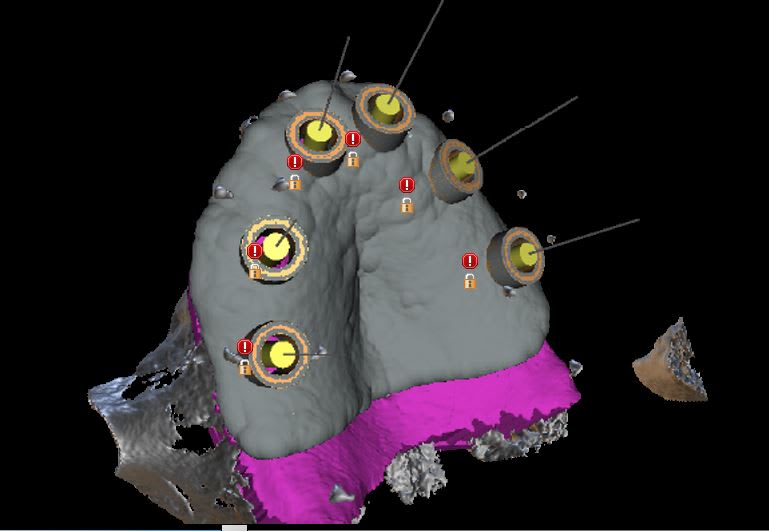

pour ceux qui ont franchi le pas ...

Capture ivkkug - Eugenol

Capture1 g1qpeb - Eugenol

Capture2 ctdd0n - Eugenol

Capture3 i5hyx6 - Eugenol

Capture4 g74a3u - Eugenol